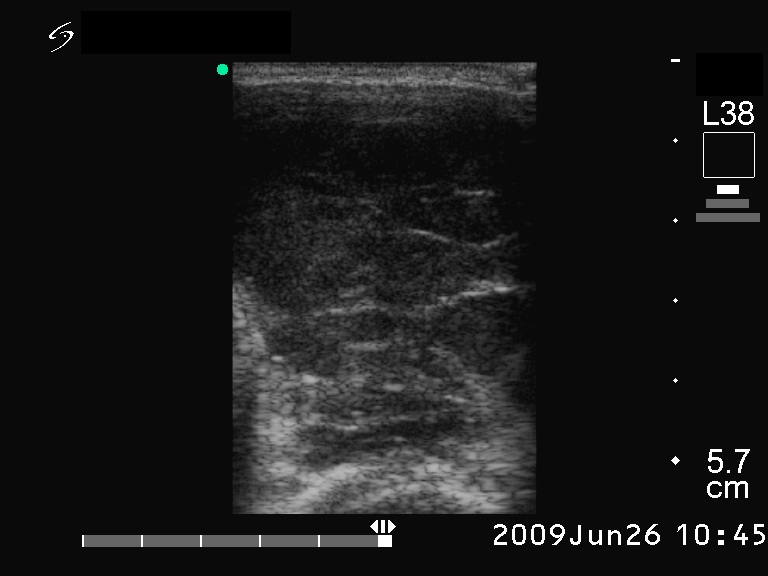

Ultrasonography. The right lobe was hypoechogenic and was not enlarged. The pattern in this lobe corresponded to Hashimoto's thyroiditis. There was a huge tumor in the left thyroid. The pattern of the left lobe varied from moderate to severe hypoechogenicity. The tumor was avascular.